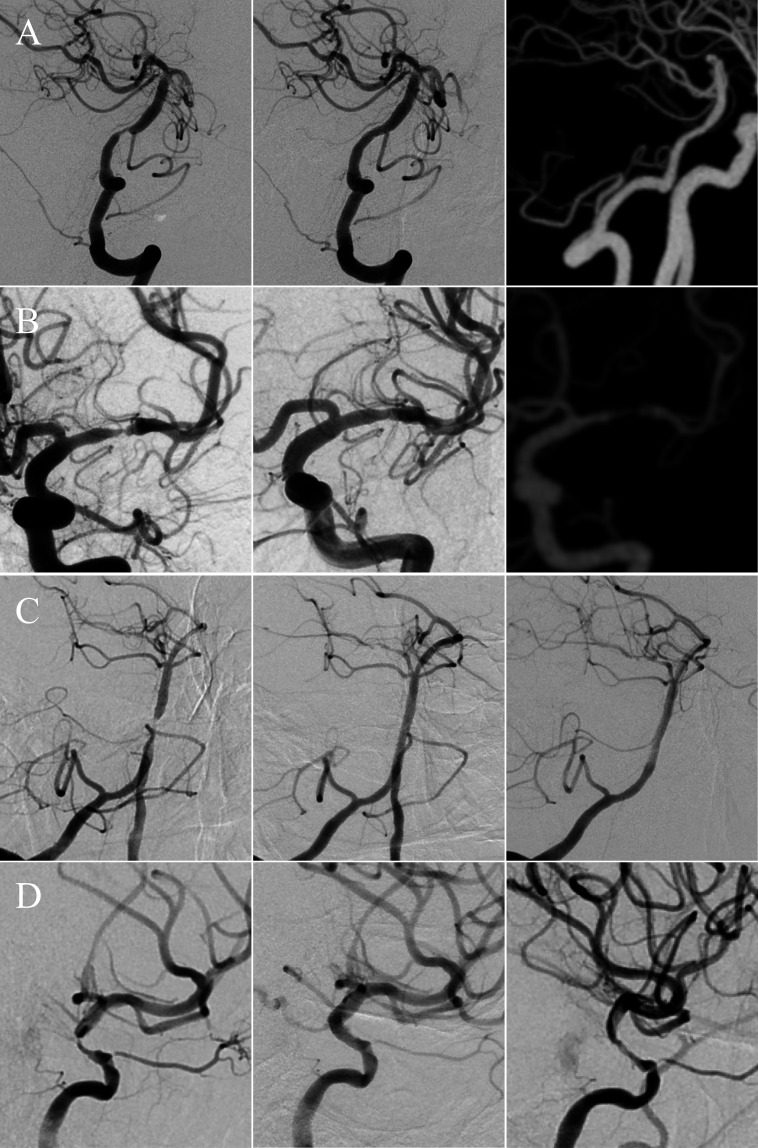

Methods: This retrospective, single-centre cohort study evaluated consecutive patients with severe sICAS who underwent intracranial stenting. Patients were categorised into four groups based on preprocedural high-sensitivity C-reactive protein (hs-CRP) and low-density lipoprotein cholesterol (LDL-C): residual cholesterol inflammatory risk (RCIR, hs-CRP ≥3 mg/L and LDL-C ≥2.6 mmol/L), RIR (hs-CRP ≥3 mg/L and LDL-C <2.6 mmol/L), residual cholesterol risk (RCR, hs-CRP <3 mg/L and LDL-C ≥2.6 mmol/L) and no residual risk (NRR, hs-CRP <3 mg/L and LDL-C <2.6 mmol/L). The long-term clinical outcomes included recurrent ischaemic stroke and death. The long-term imaging outcomes consisted of in-stent restenosis (ISR) and symptomatic ISR (sISR) after stenting.

Results: In this study, 952 patients were included, with 751 (78.9%) being male. Forty-six cases were categorised into the RCIR group, 211 into the RIR group, 107 into the RCR group and 588 into the NRR group. Patients with RCIR (adjusted HR 6.163; 95% CI 2.603 to 14.589; p<0.001) and RIR (adjusted HR 2.205; 95% CI 1.294 to 3.757; p=0.004) had higher risks of recurrent ischaemic stroke than those with NRR during the 54 months of median follow-up time. Patients with RCIR (adjusted HR 3.604; 95% CI 1.431 to 9.072; p=0.007) were more likely to occur ISR, and patients in the RIR group showed a significant increase in the risk of sISR (adjusted HR 2.402; 95% CI 1.078 to 5.351; p=0.032) compared with those in the NRR group with a median follow-up time of 11.9 months.

Conclusions: In patients with sICAS, preprocedural RIR may predict long-term recurrent ischaemic stroke, ISR and sISR following intracranial stenting.